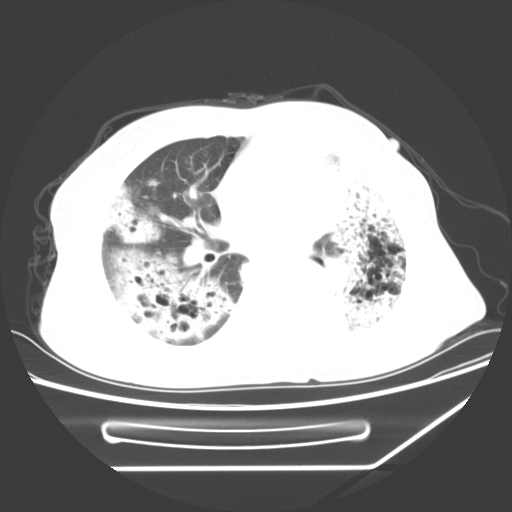

标题: CT25393:病人45岁,咳嗽,吐黄痰带血丝,发热,胸闷月余 [打印本页]

标题: CT25393:病人45岁,咳嗽,吐黄痰带血丝,发热,胸闷月余

1、左肺中央型肺癌并双肺弥漫性转移   2、双肺部感染    3、肺大泡     4、左侧胸腔积液

双侧肺弥漫性病变,可见“空泡征”及“蜂窝征”,考虑肺泡癌可能性大,左侧胸腔积液,考虑胸膜受累可能!

考虑肺泡癌,建议排除感染。

考虑肺泡癌

1)不排除肺泡癌可能。2)左侧胸腔积液。